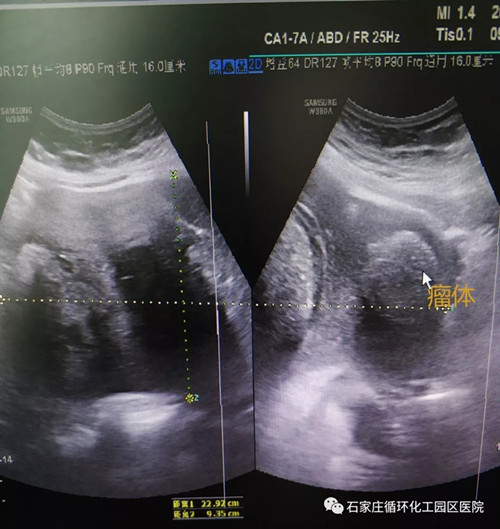

7月9日,園區(qū)醫(yī)院婦產(chǎn)科迎來了一位小腹不適的47歲女性,她的檢查結果令醫(yī)務人員震驚。盆腔彩超檢查發(fā)現(xiàn)附件囊實性較大包塊,CT檢查顯示下腹部有較大腫塊。一個22.9公分的巨大卵巢畸胎瘤安穩(wěn)地躺在患者的腹盆腔內(nèi),嚴重吞噬著患者的健康。

盆腔彩超影像